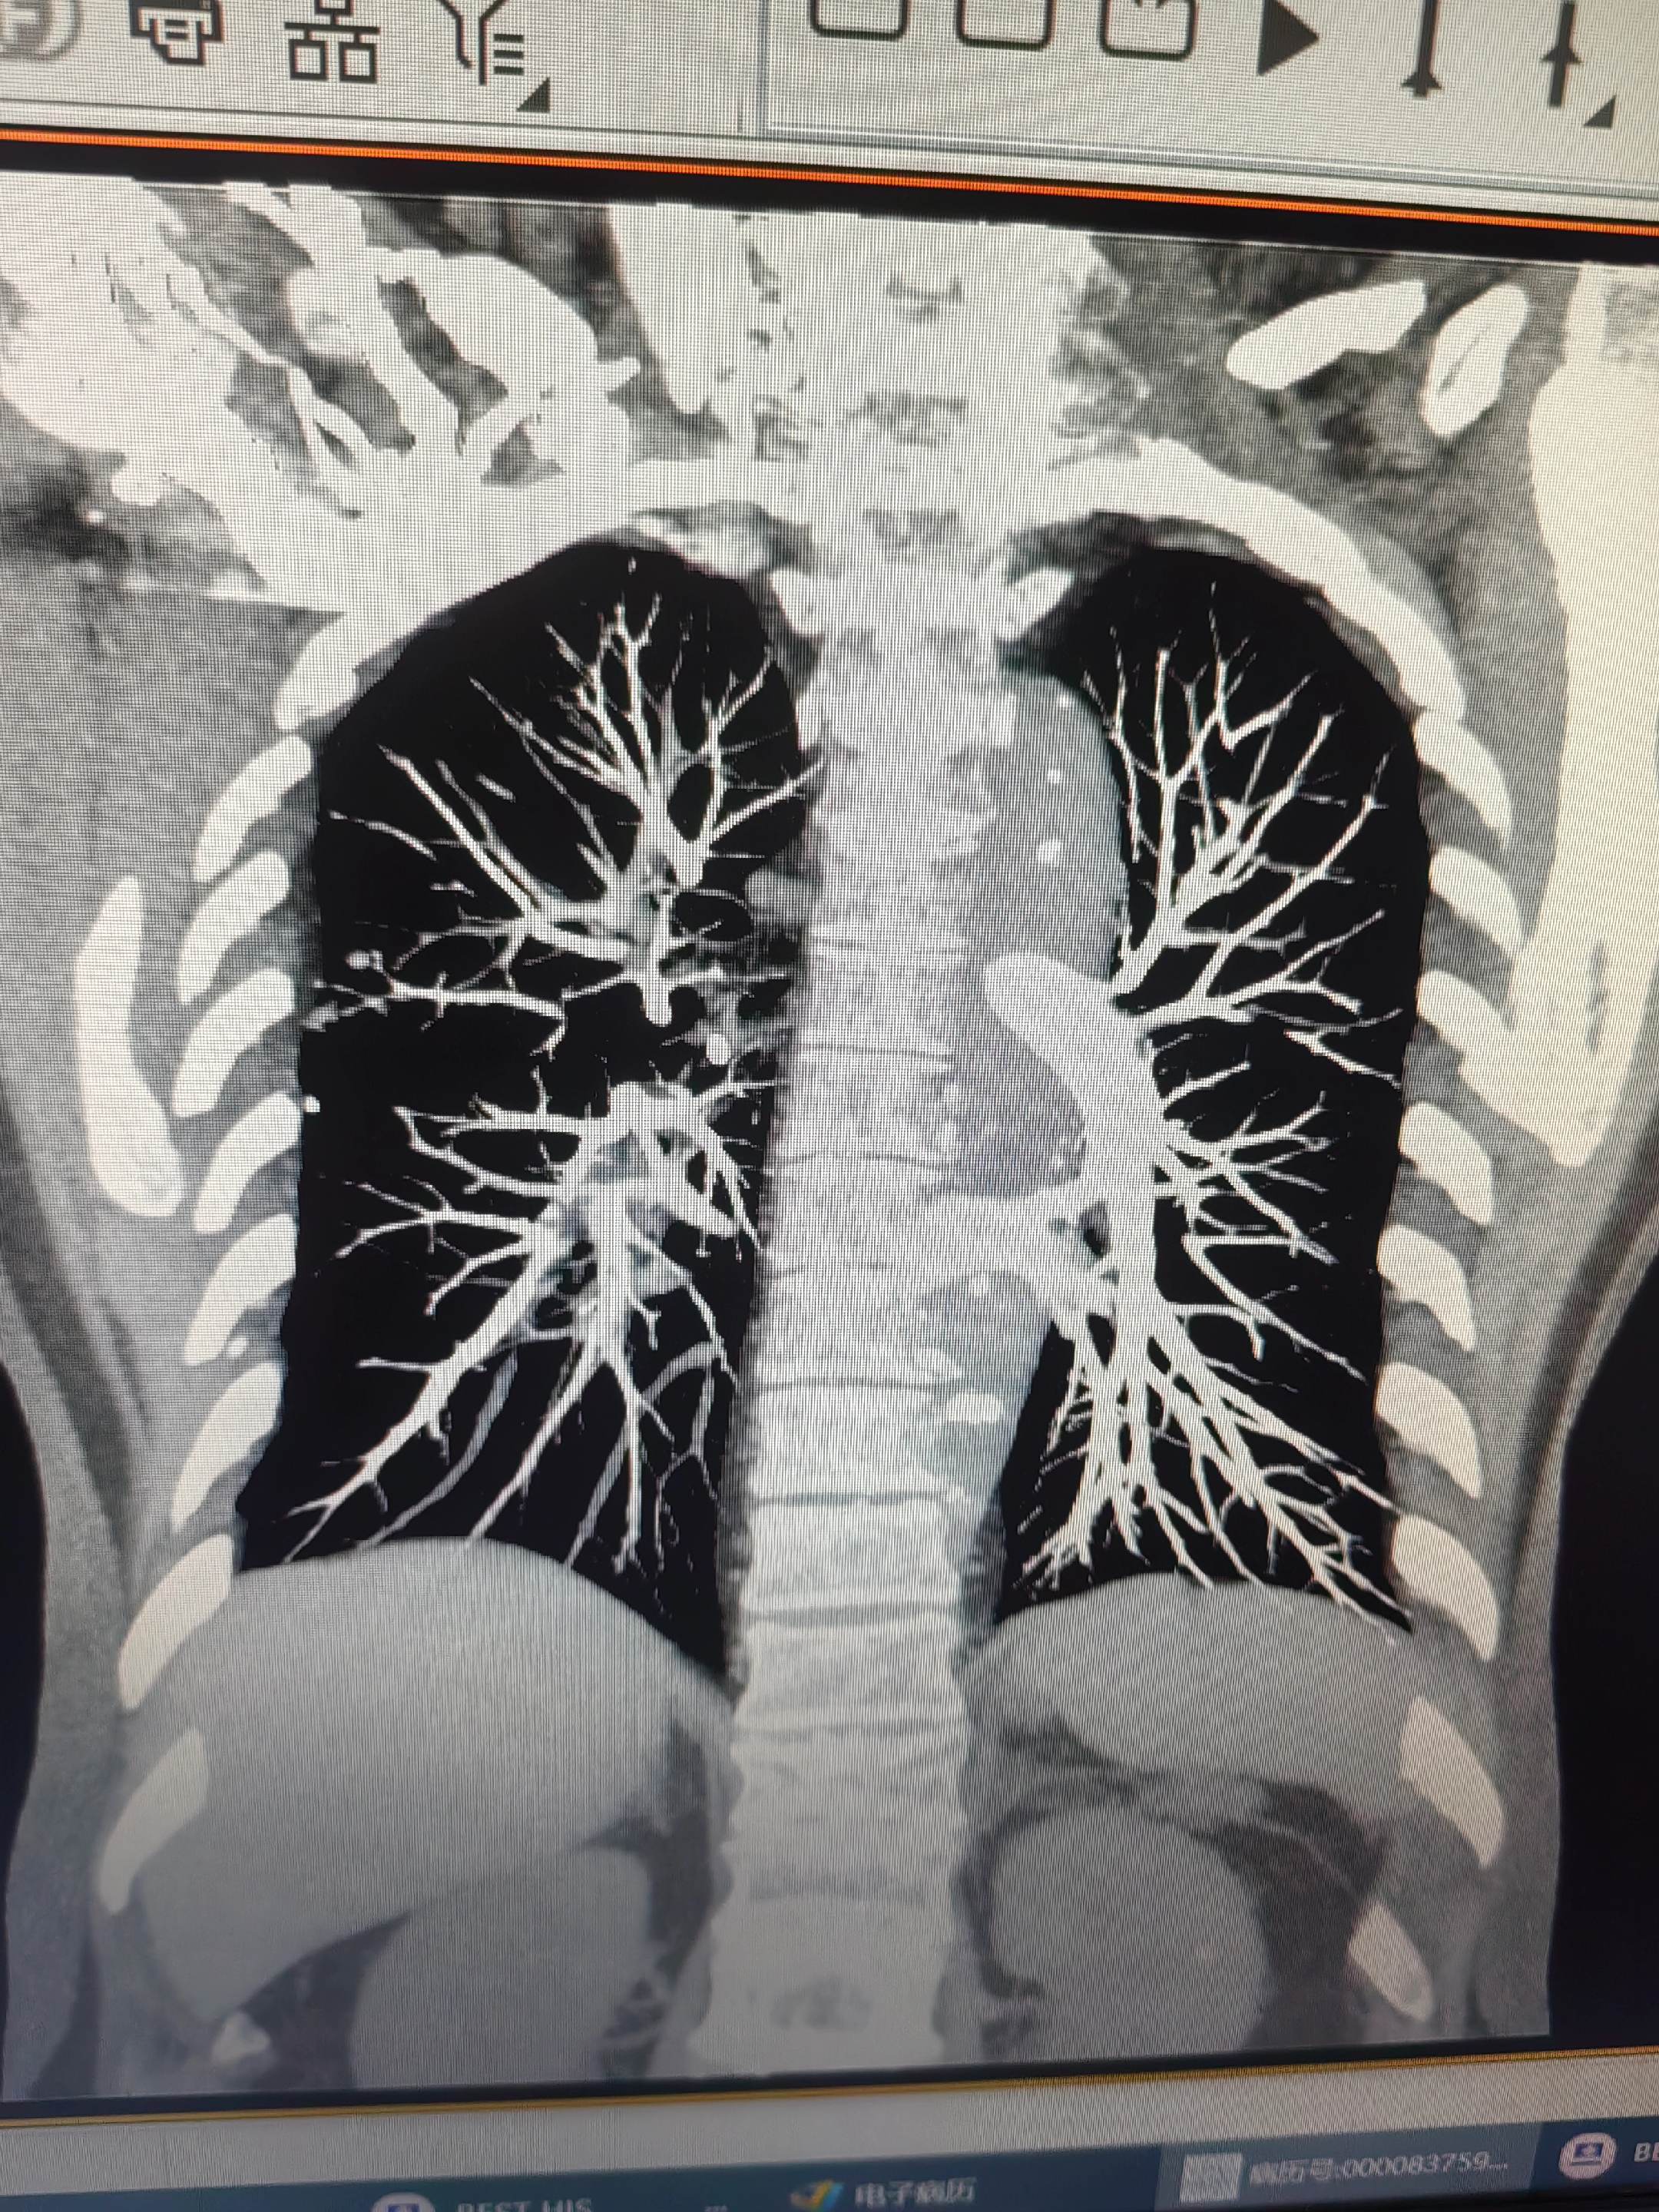

肺栓塞。